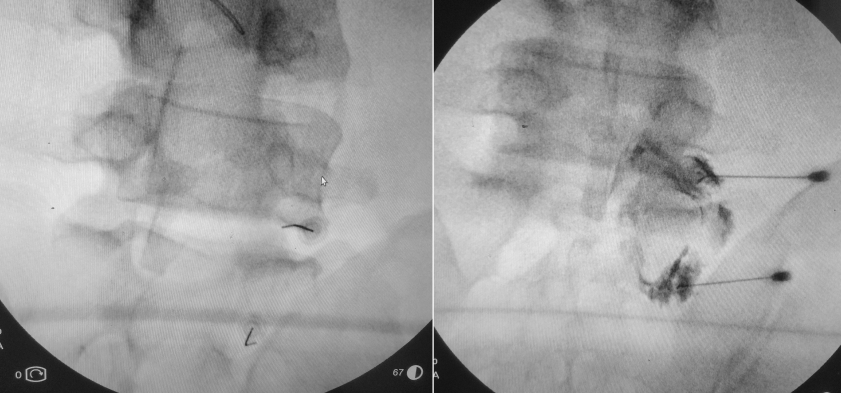

Sağ L5-S1 forameni ve S1 foramenleri yoluyla epidural enjeksiyon uygulanması. Enjeksiyon ameliyathanede, hasta yüzüstü

pozisyonda karın altı desteklenerek, skopi altında ve kontrast madde kontrolü

ile (300 mg/ml Ultravist), 20G kalınlığında ve 9 cm uzunlugunda spinal

iğneler kullanılarak steril teknikle uygulandı. Toplam 20-30 ml hacminde olmak

üzere %1 adrenalinsiz Lidokain + serum fizyolojik + ½ ampul depo steroid verildi. L5-S1

seviyesinde infranöral teknik kullanılmıştır. Sağdaki resimde her iki

foramenden de epidural alana uygun kontrast geçişi görülmekte. Daha iyi

ağrı kontrolü amacıyla aynı seansta sağda L2-S1 medial dal blokları da

yapıldı.